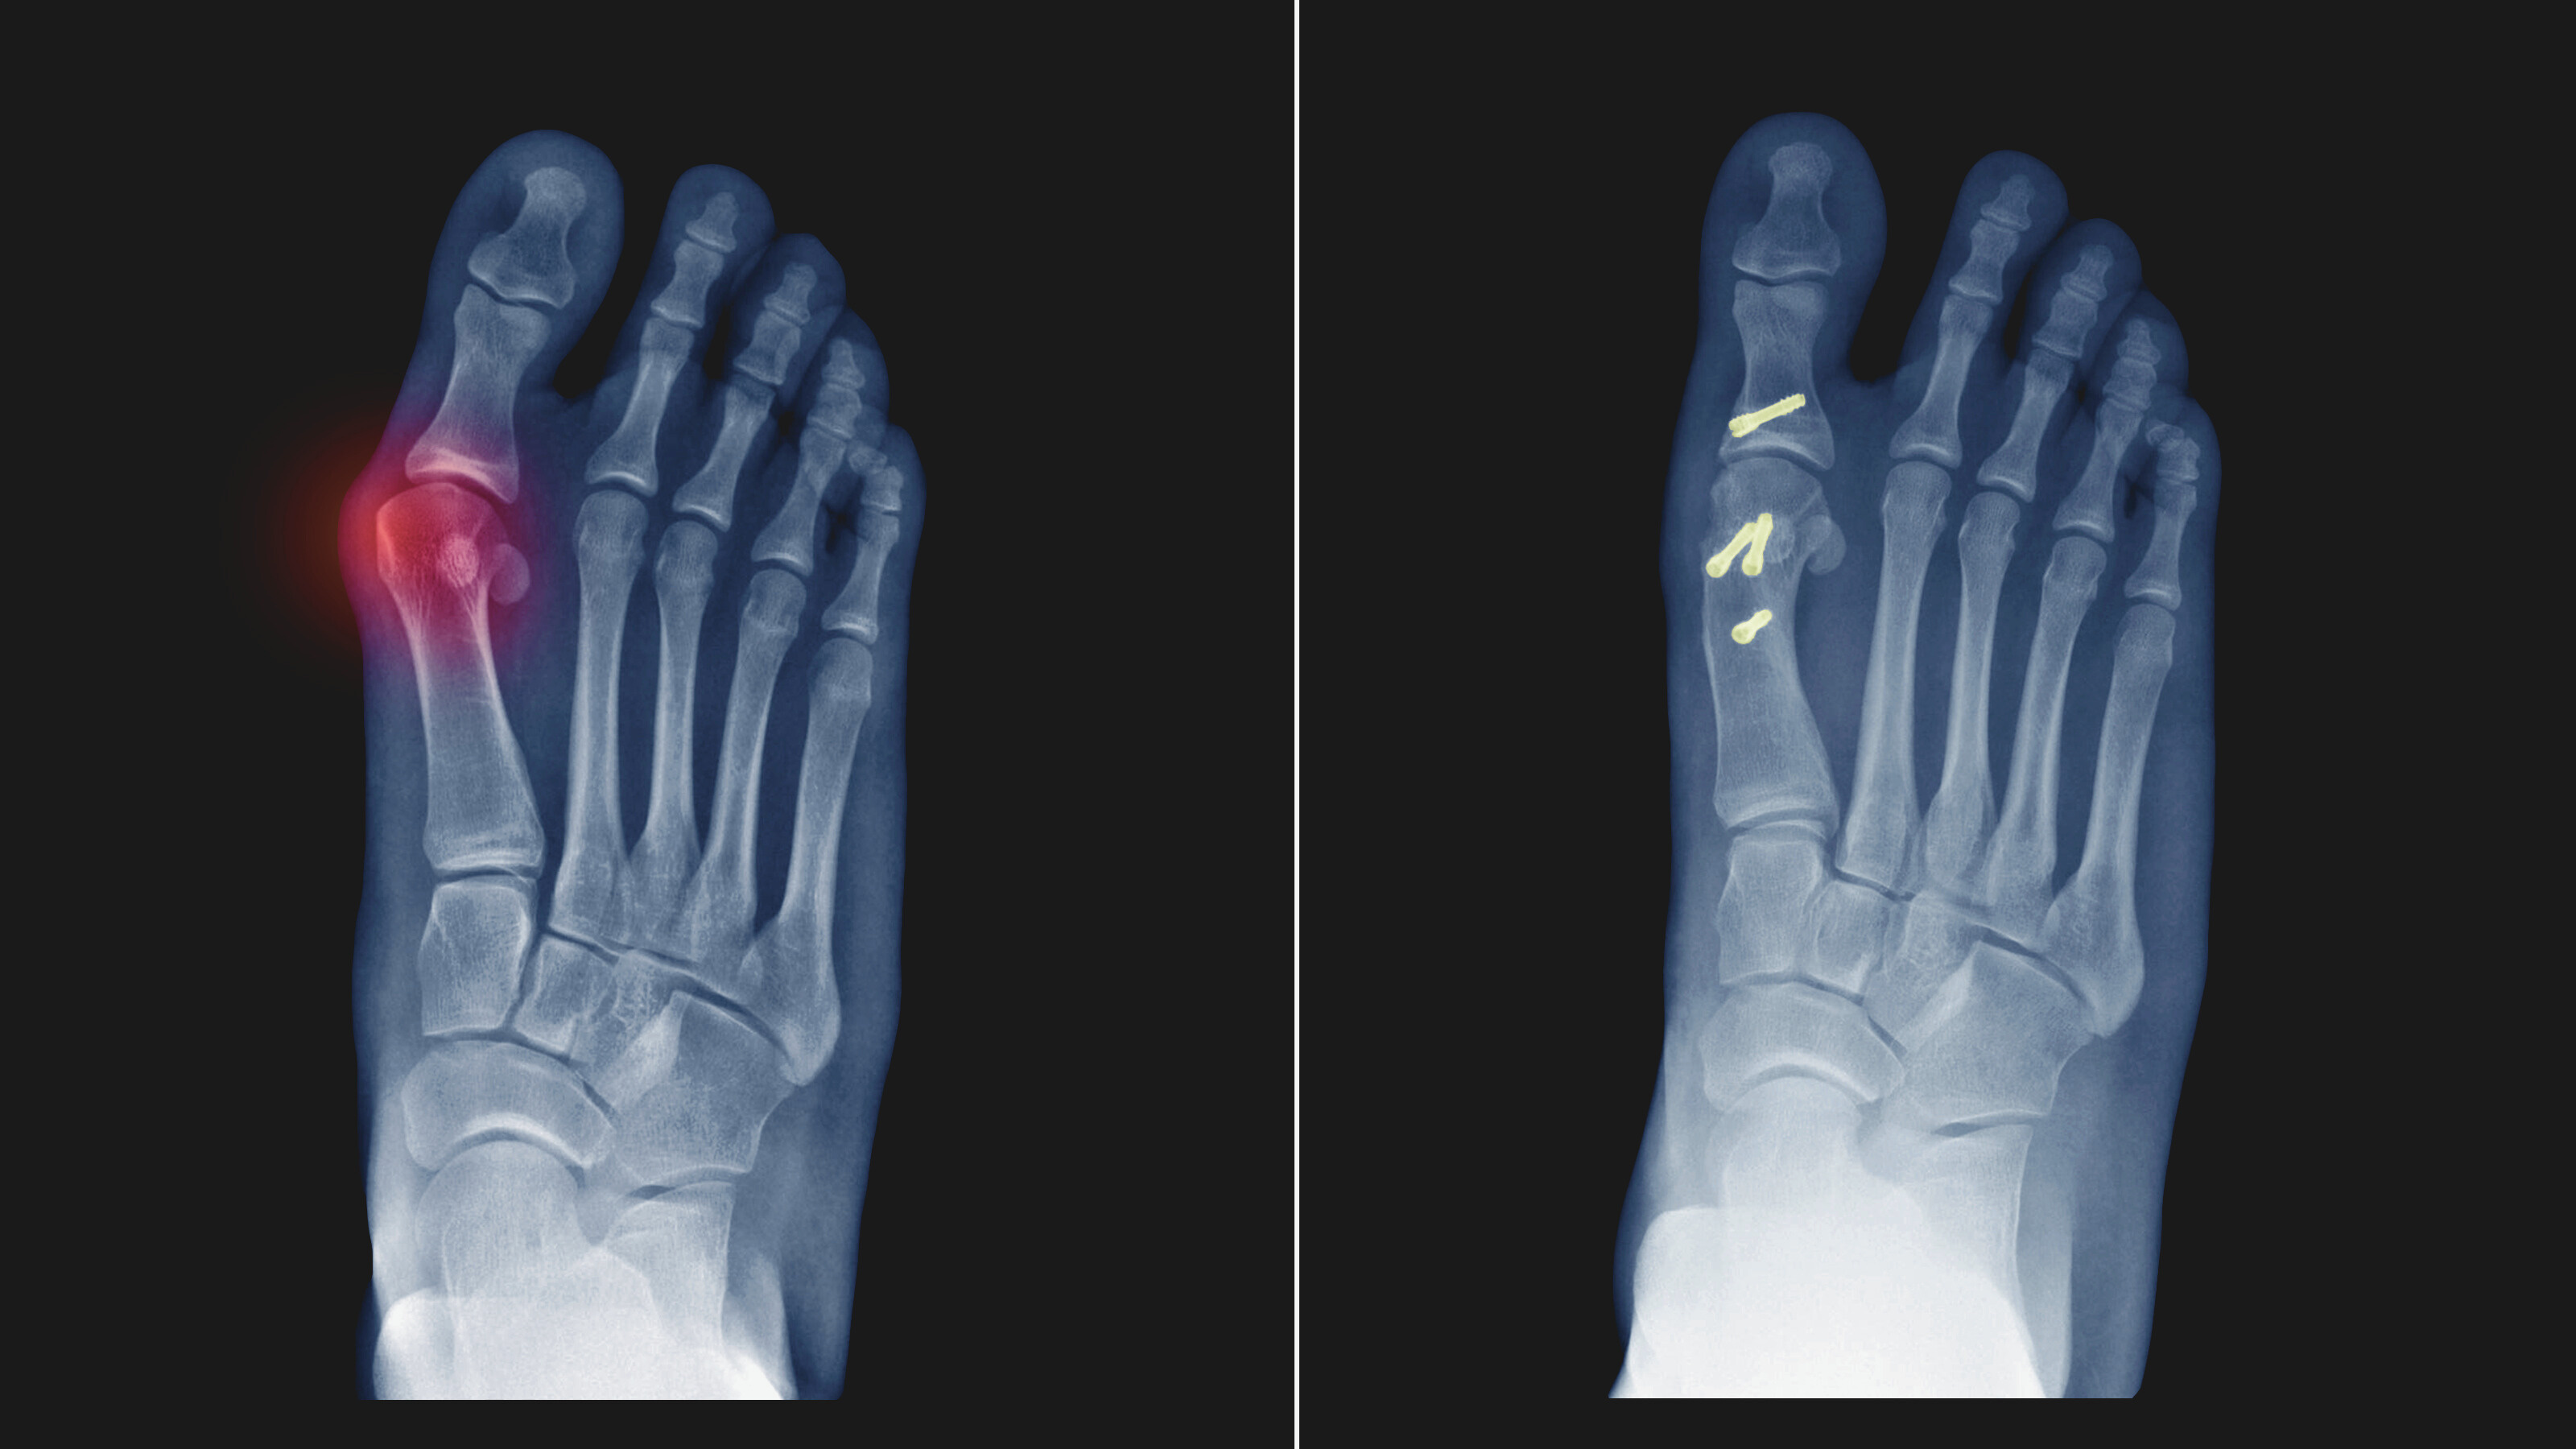

レントゲン・MRI検査

膝関節症の症状を確認するためのMRI検査(外部機関)と足の骨格姿勢を荷重下レントゲンで検査。